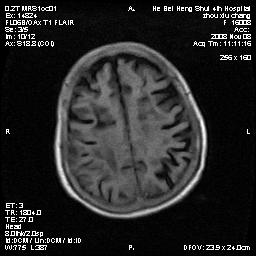

标题: MRI1883:女67岁,半年前曾患脑梗塞,治疗后好转,近3各月精 [打印本页]

标题: MRI1883:女67岁,半年前曾患脑梗塞,治疗后好转,近3各月精

女67岁,半年前曾患脑梗塞,治疗后好转,近3各月精神恍惚。